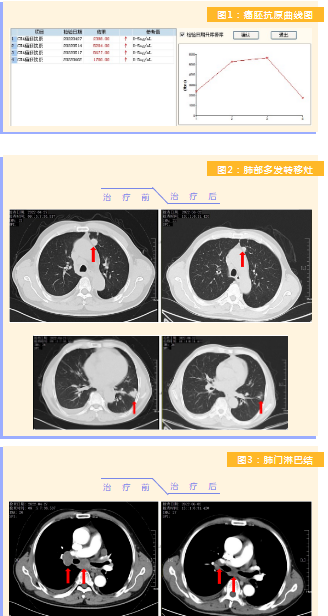

患者完成1周期治療后,上腹部疼痛癥狀基本消失,梗阻性黃疸癥狀緩解,腫瘤指標(biāo)下降(圖1),肺部多發(fā)轉(zhuǎn)移灶消失和縮?。▓D2),雙肺門淋巴結(jié)縮?。▓D3),肝臟多發(fā)轉(zhuǎn)移灶縮?。▓D4)。